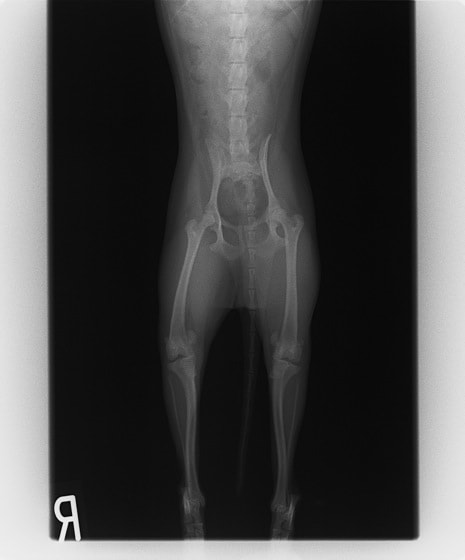

■ 症例24 キャバリア 7か月

左右膝蓋骨内方脱臼(左:グレードⅣ 右:グレードⅢ)

以前から左右後肢の跛行が認められ、整形外科学的検査・レントゲン検査により左右の膝蓋骨脱臼が認められた。症状が重度である左膝の膝蓋骨脱臼整復術を行った。外科手技は縫工筋及び内側広筋の解放、脛骨粗面の外側転位、滑車ブロック形造溝術、内外側関節方の縫縮を実施した。術後一か月時点で、左の膝蓋骨は安定しており経過は良好である。

本症例は成長期における重度の膝蓋骨脱臼であり、術後の再発の可能性もあるため、経過をしっかりと観察していく必要がある。また、今回手術を実施していない右膝に関しても経過を観察し、手術を検討していくこととする。